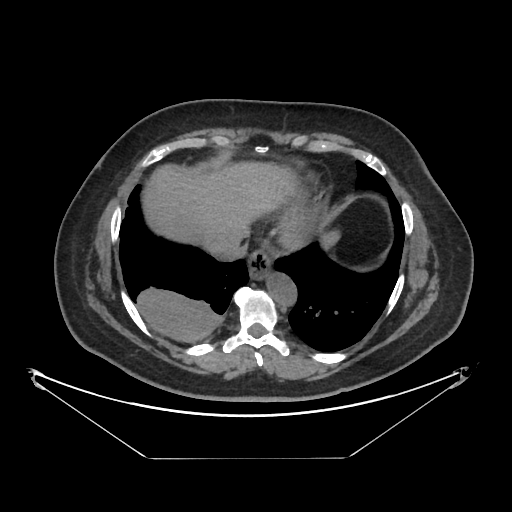

Generated VENOUS CT scan (A→B translation)

Full window (WL 1023.5, WW 4095 β†’ Low βˆ’1024, High +3071)

Actual HU range: [-1024.0, 897.0]